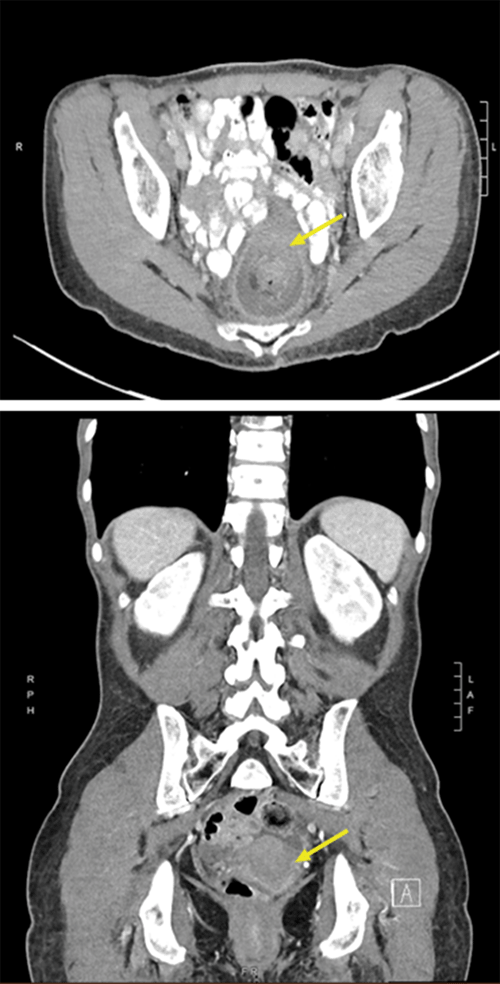

Figure 2.  Axial (top) and Coronal (bottom) Cross-sections of Repeat CT Scan With Intravenous Contrast on Date of Presentation. Published With Permission

CT demonstrates 'telescoping' of sigmoid colon, along with its mesentery and vessels into rectum (arrow). No pneumatosis or pneumoperitoneum found despite mild bowel edema of sigmoid intussuscipiens. CT also noteworthy for prominent left external iliac and sigmoid mesentery lymph nodes.